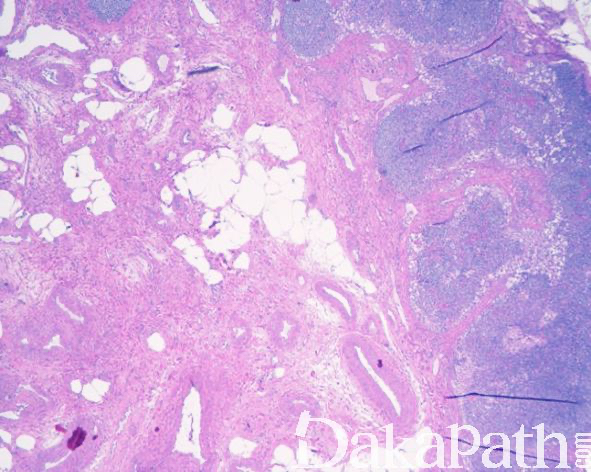

组织学表现为淋巴结实质内的血管肌样增生伴有不同比例的纤维性间质,血管壁通常较厚,管腔大小不等,平滑肌样梭形细胞形态较温和,具有嗜酸性胞浆和顿圆的核,呈疏松或致密的束状排列,无核分裂象和坏死;2/3 的病例内可见散在或广泛呈簇分布的成熟脂肪组织;

较大的病变常弥漫取代淋巴结实质或病变内可见残存的岛状淋巴组织,较小的病变多位数淋巴结中央或门部,周围绕以未受累的淋巴组织;